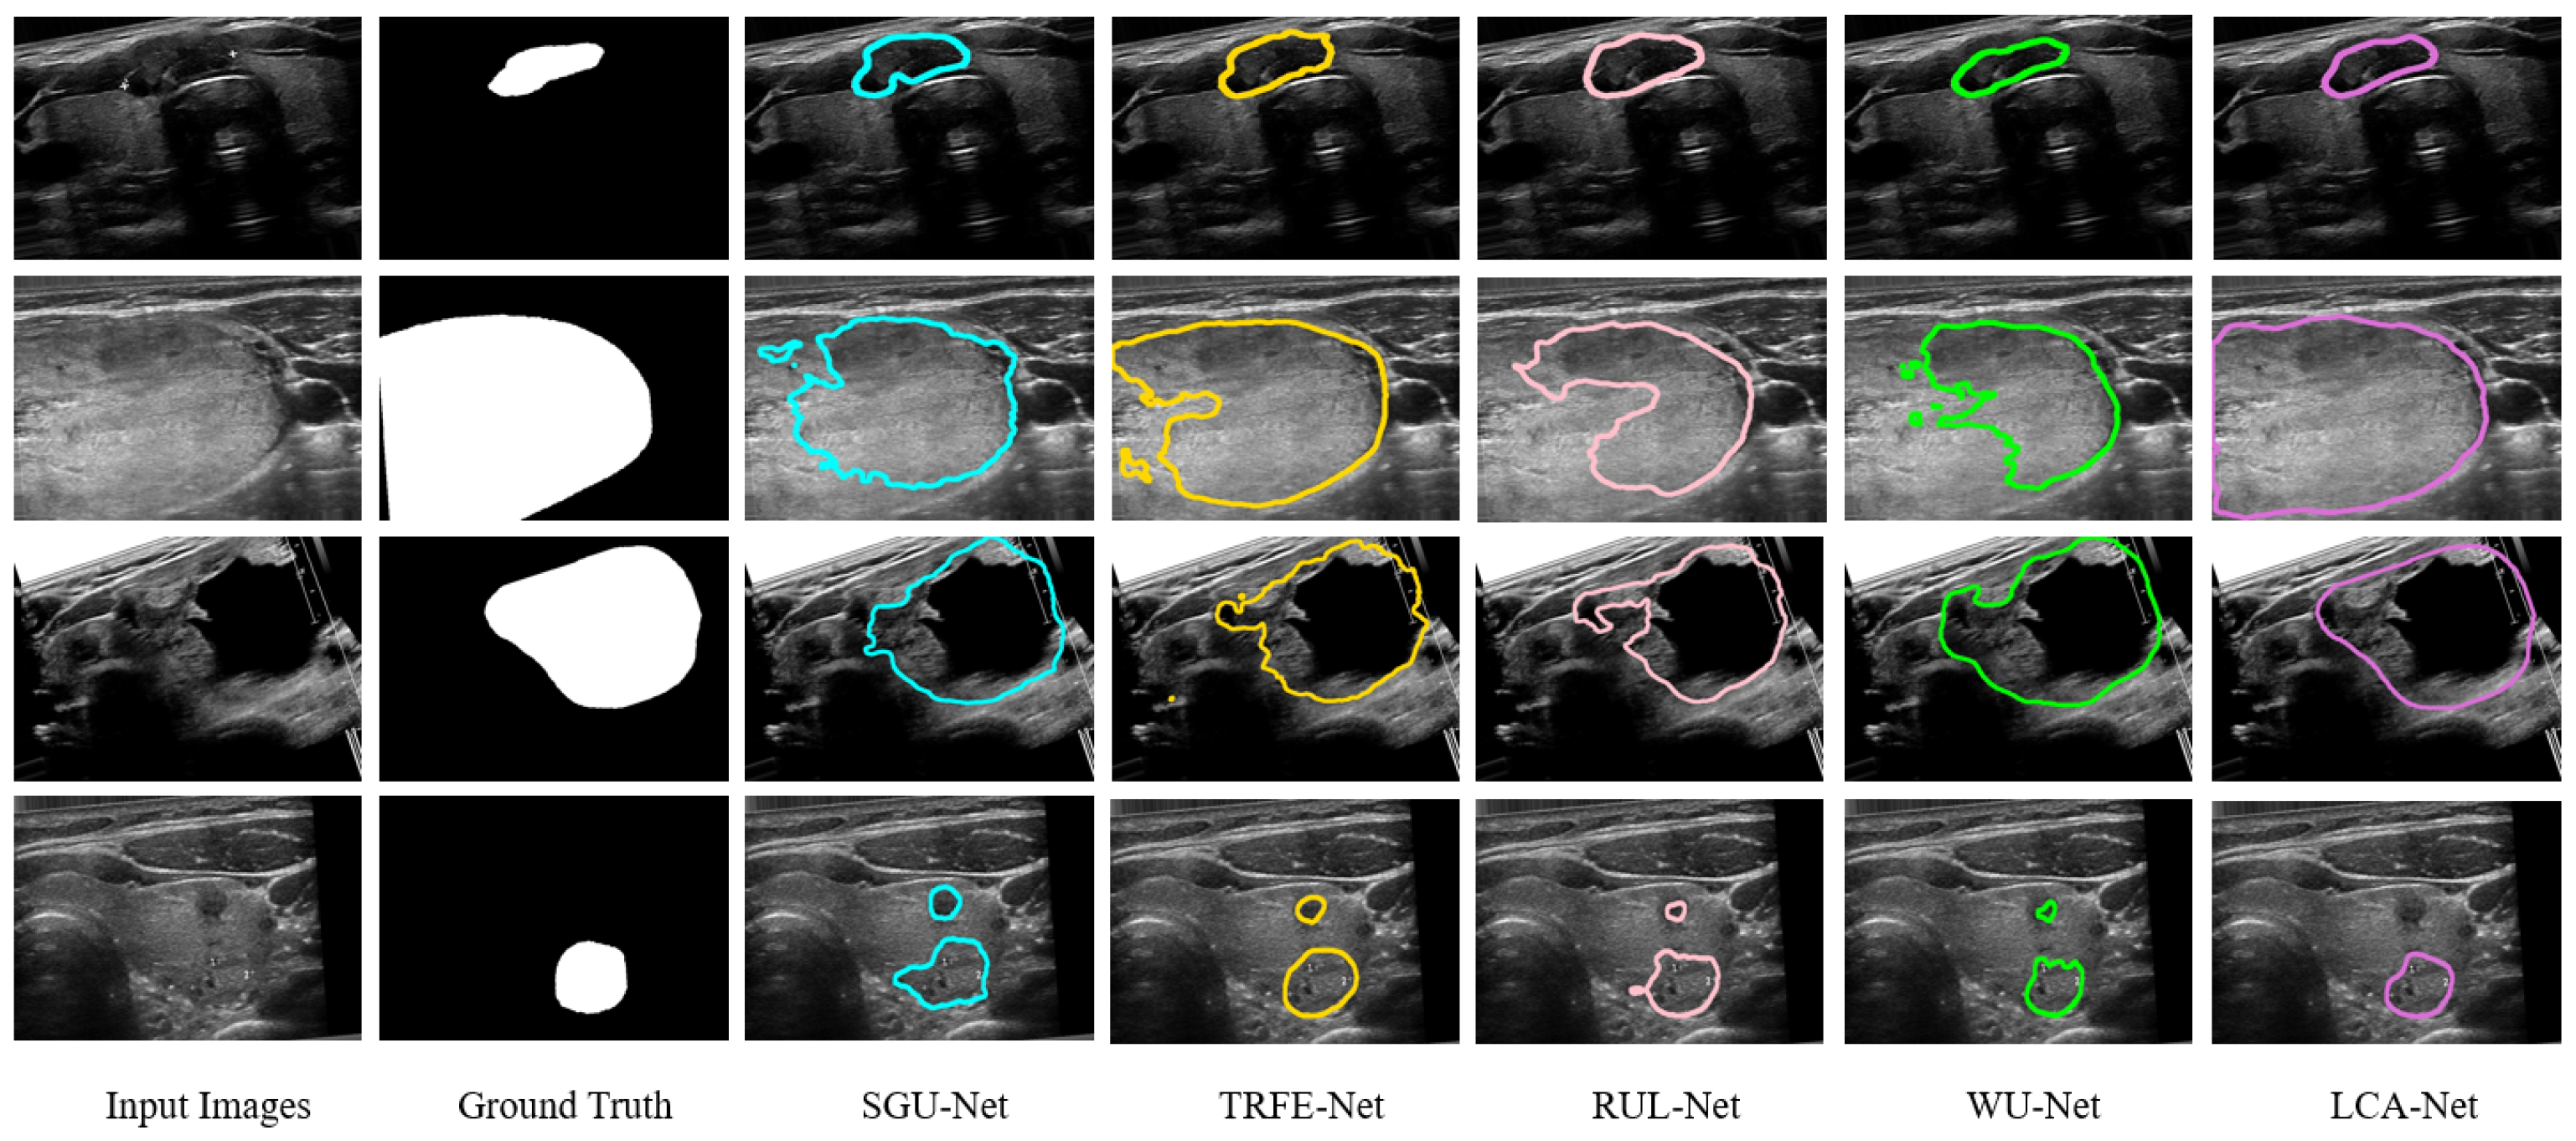

3.4. Comparison to State-of-the-Art Models